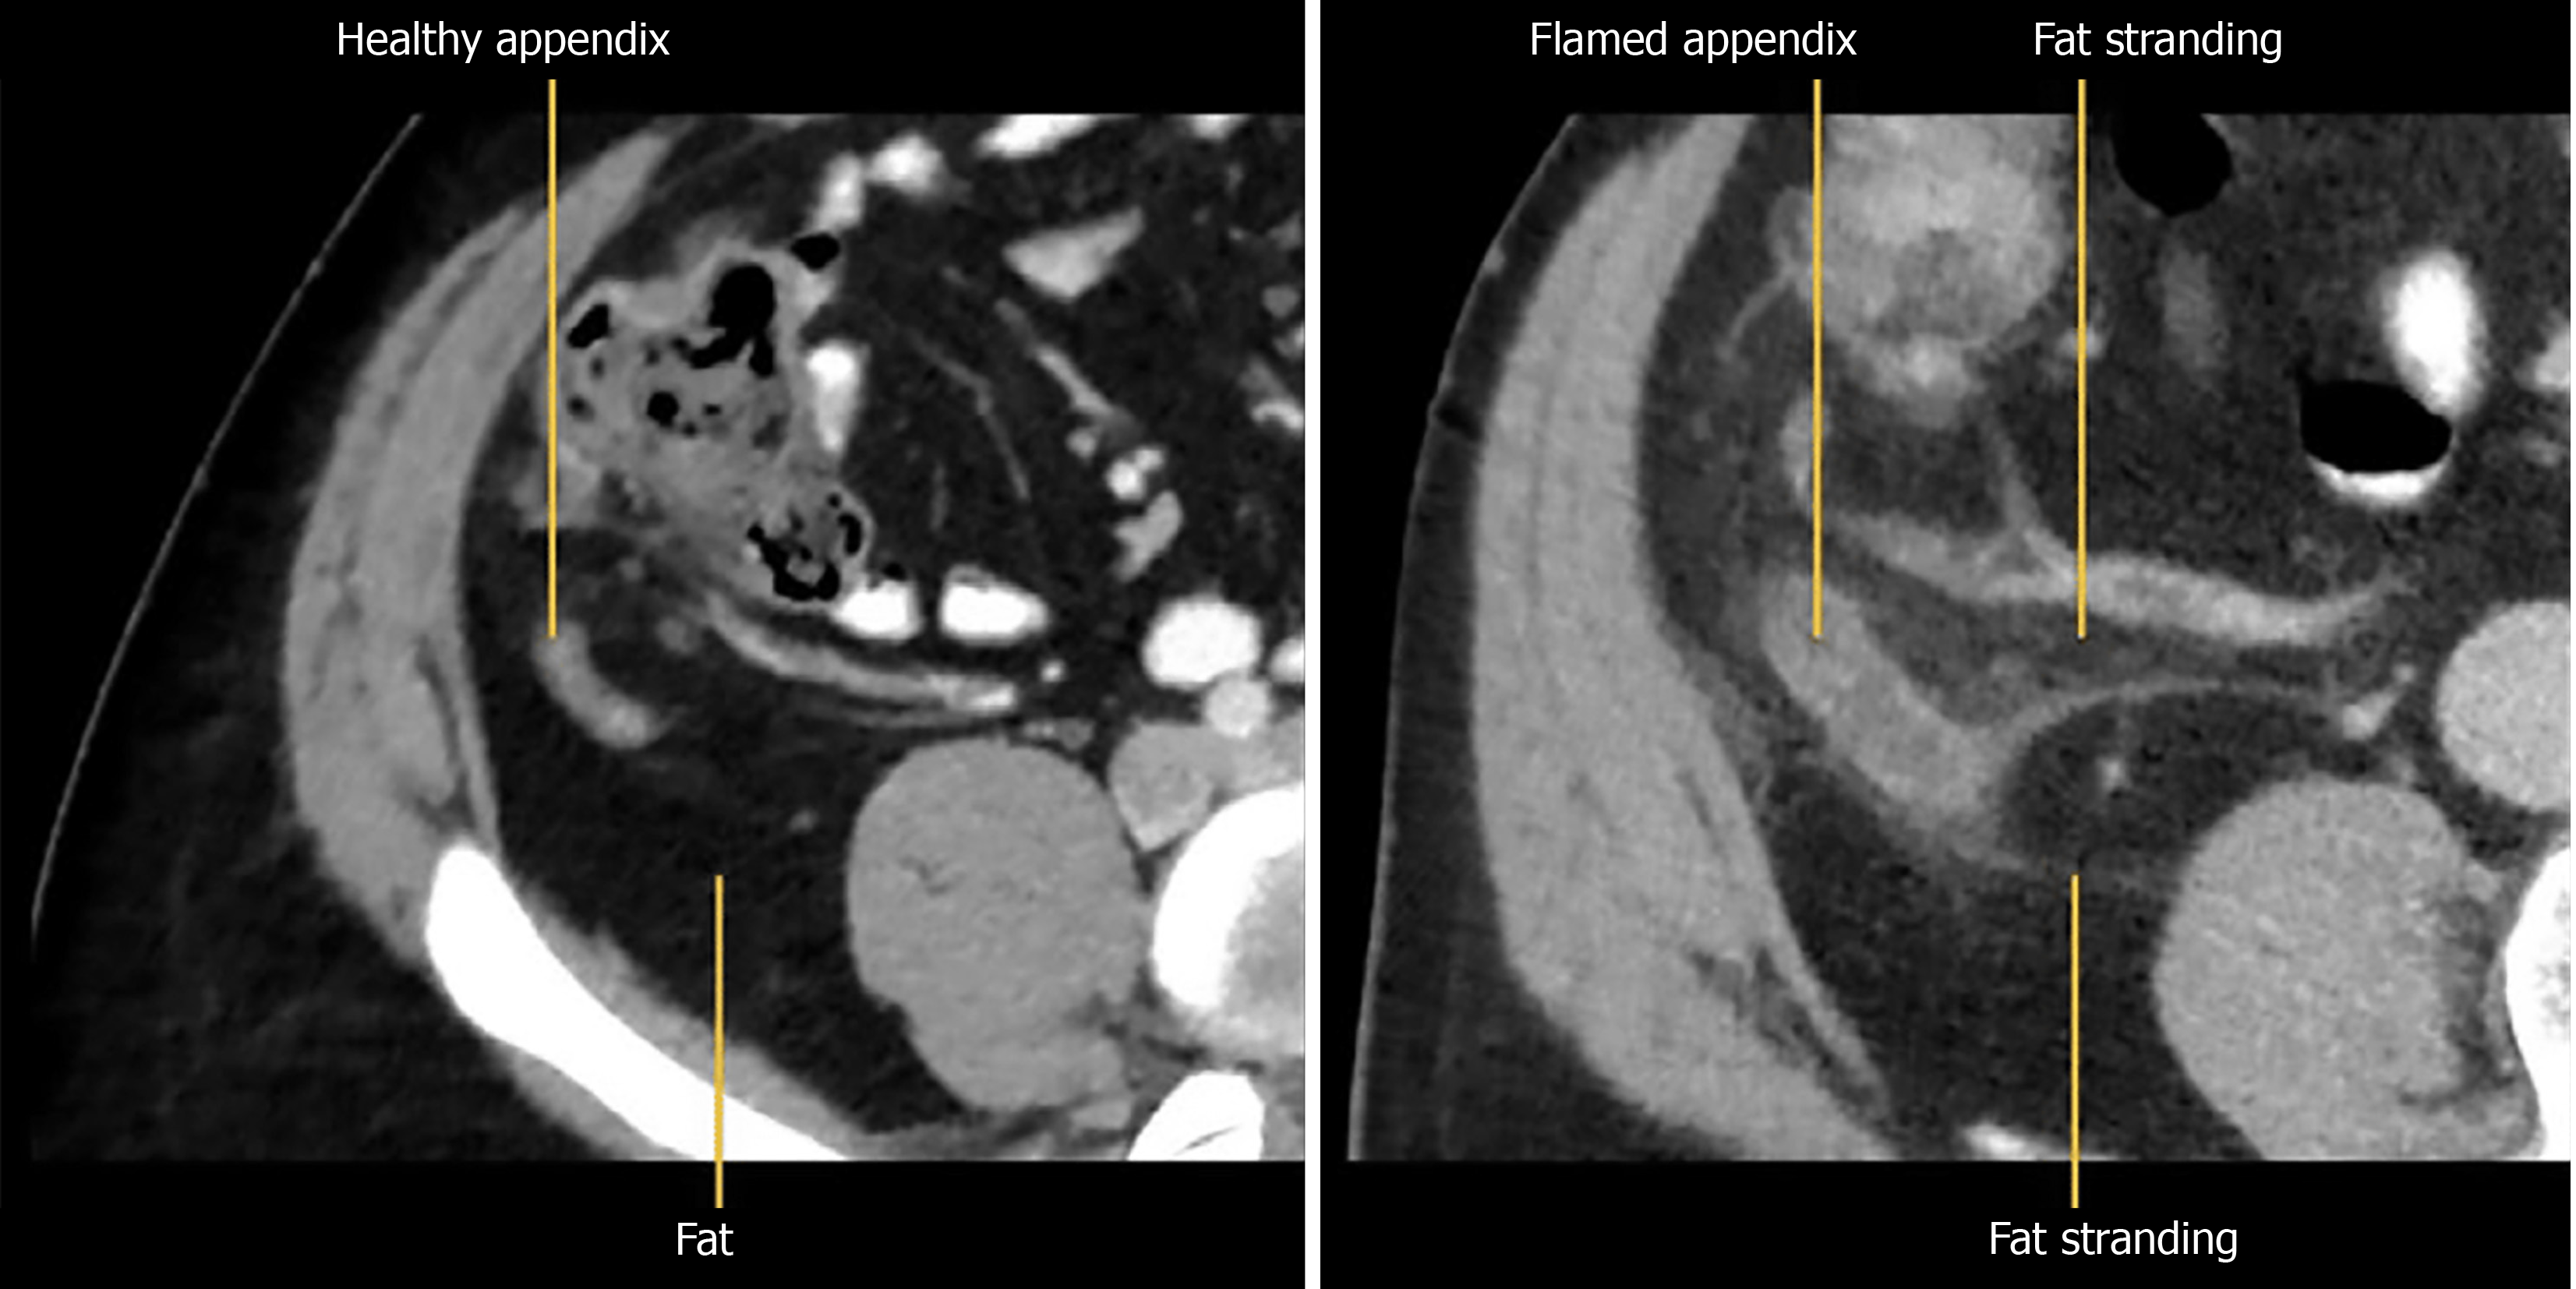

Among these secondary signs, peri-appendiceal fat stranding and fluid collections signify localized inflammation (Figure 1). The stranding appears as bright, inflamed fat surrounding the appendix and often correlates with symptom severity[10]. Wall thickening greater than 3 mm and hyperenhancement following contrast administration are additional indicators of appendicitis (Figure 2A)[11]. A particularly specific but less common finding is the presence of airless, low-attenuation fluid within the lumen (Figure 2B). This fluid type is rare in normal appendices and may signify early mucosal involvement. A threshold of 2.6 mm of fluid within the appendix has shown strong diagnostic performance[9,12].

Figure 1

Figure 1 On the left is a computed tomography image of normal healthy appendix while on the right is an inflamed appendix with fat stranding.